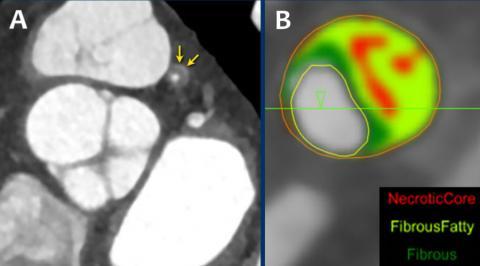

signs of high risk plaque on CTA

napkin ring sign (high risk plaque)